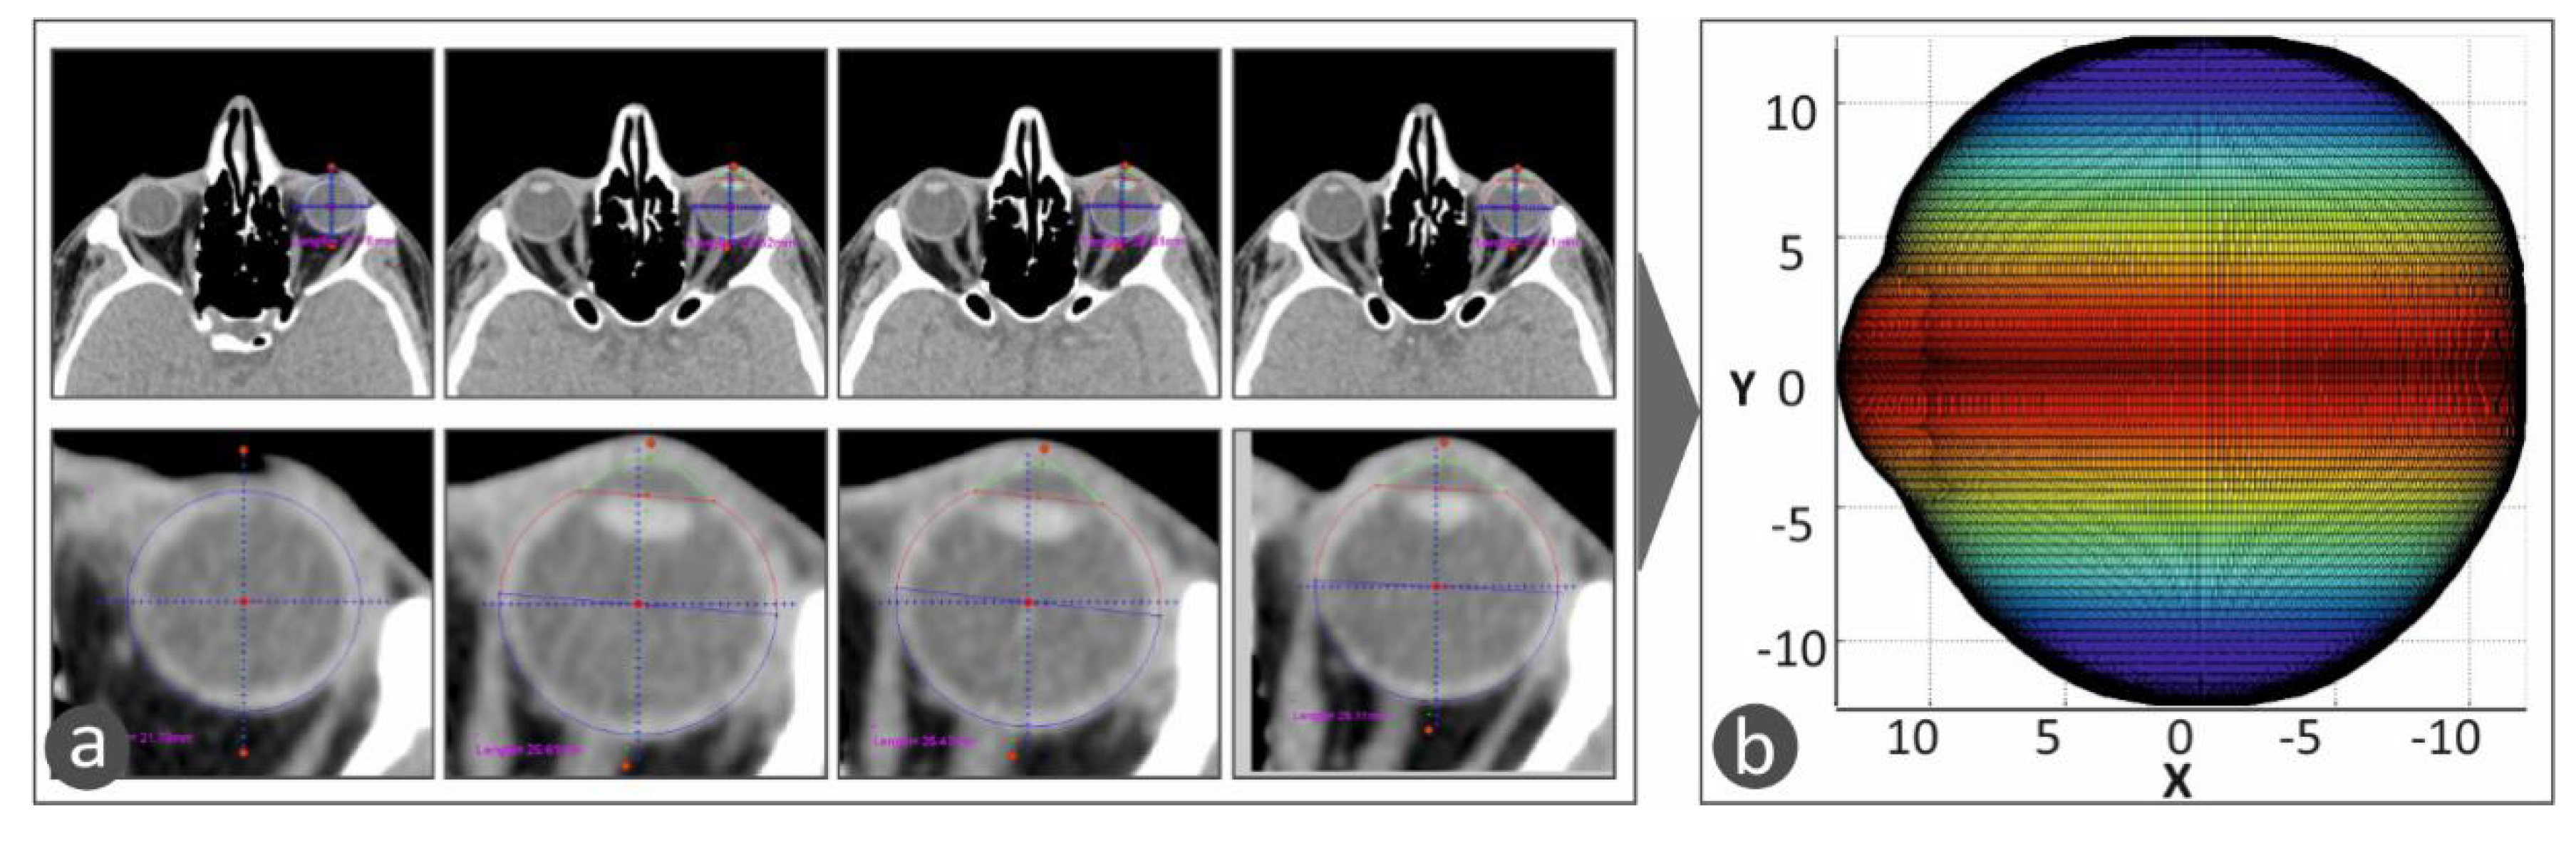

These algorithms were developed, and the CT images were processed in the Matlab Student software (Mathworks, MA, USA), which provides integrated tools and flexibility in reading and editing the tomography images. All the CT images were scanned, one by one, and the perimeter of the specific eye was acquired from each slice. The algorithm considers any movement of the patient or the patient’s eye during the scan in order to avoid developing distorted geometric models during the procedure to capture the human anatomy of each patient. Taking into consideration the slice thickness, the space between slices, and the pixel spacing, a three-dimensional geometric model of the eye was developed. The three-dimensional representation of the eye shows the iris and the quadrants of the eye. This representation of the 3D geometry helps the operator position the macular buckle accurately (Figure 3). Figure 3a shows typical CT images, in which the perimeter of the eye is determined and acquired for the determination of the 3D geometry of the eye. Figure 3b shows the 3D geometric model determined from the CT scan images and represented with a color scale. The color scale at this face of the work was used in the vertical direction to show the human eye height vs. the change in the human eye section size in the horizontal direction.

Figure 3. The 3D model of the human eye in the developed software. A color scale was used in the vertical direction to show the human eye height vs. the change in the human eye section size in the horizontal direction: (a) CT scan images in which the perimeter of the eye is determined and acquired, (b) 3D geometric model of the eye determined from the CT scan images and represented with a color scale